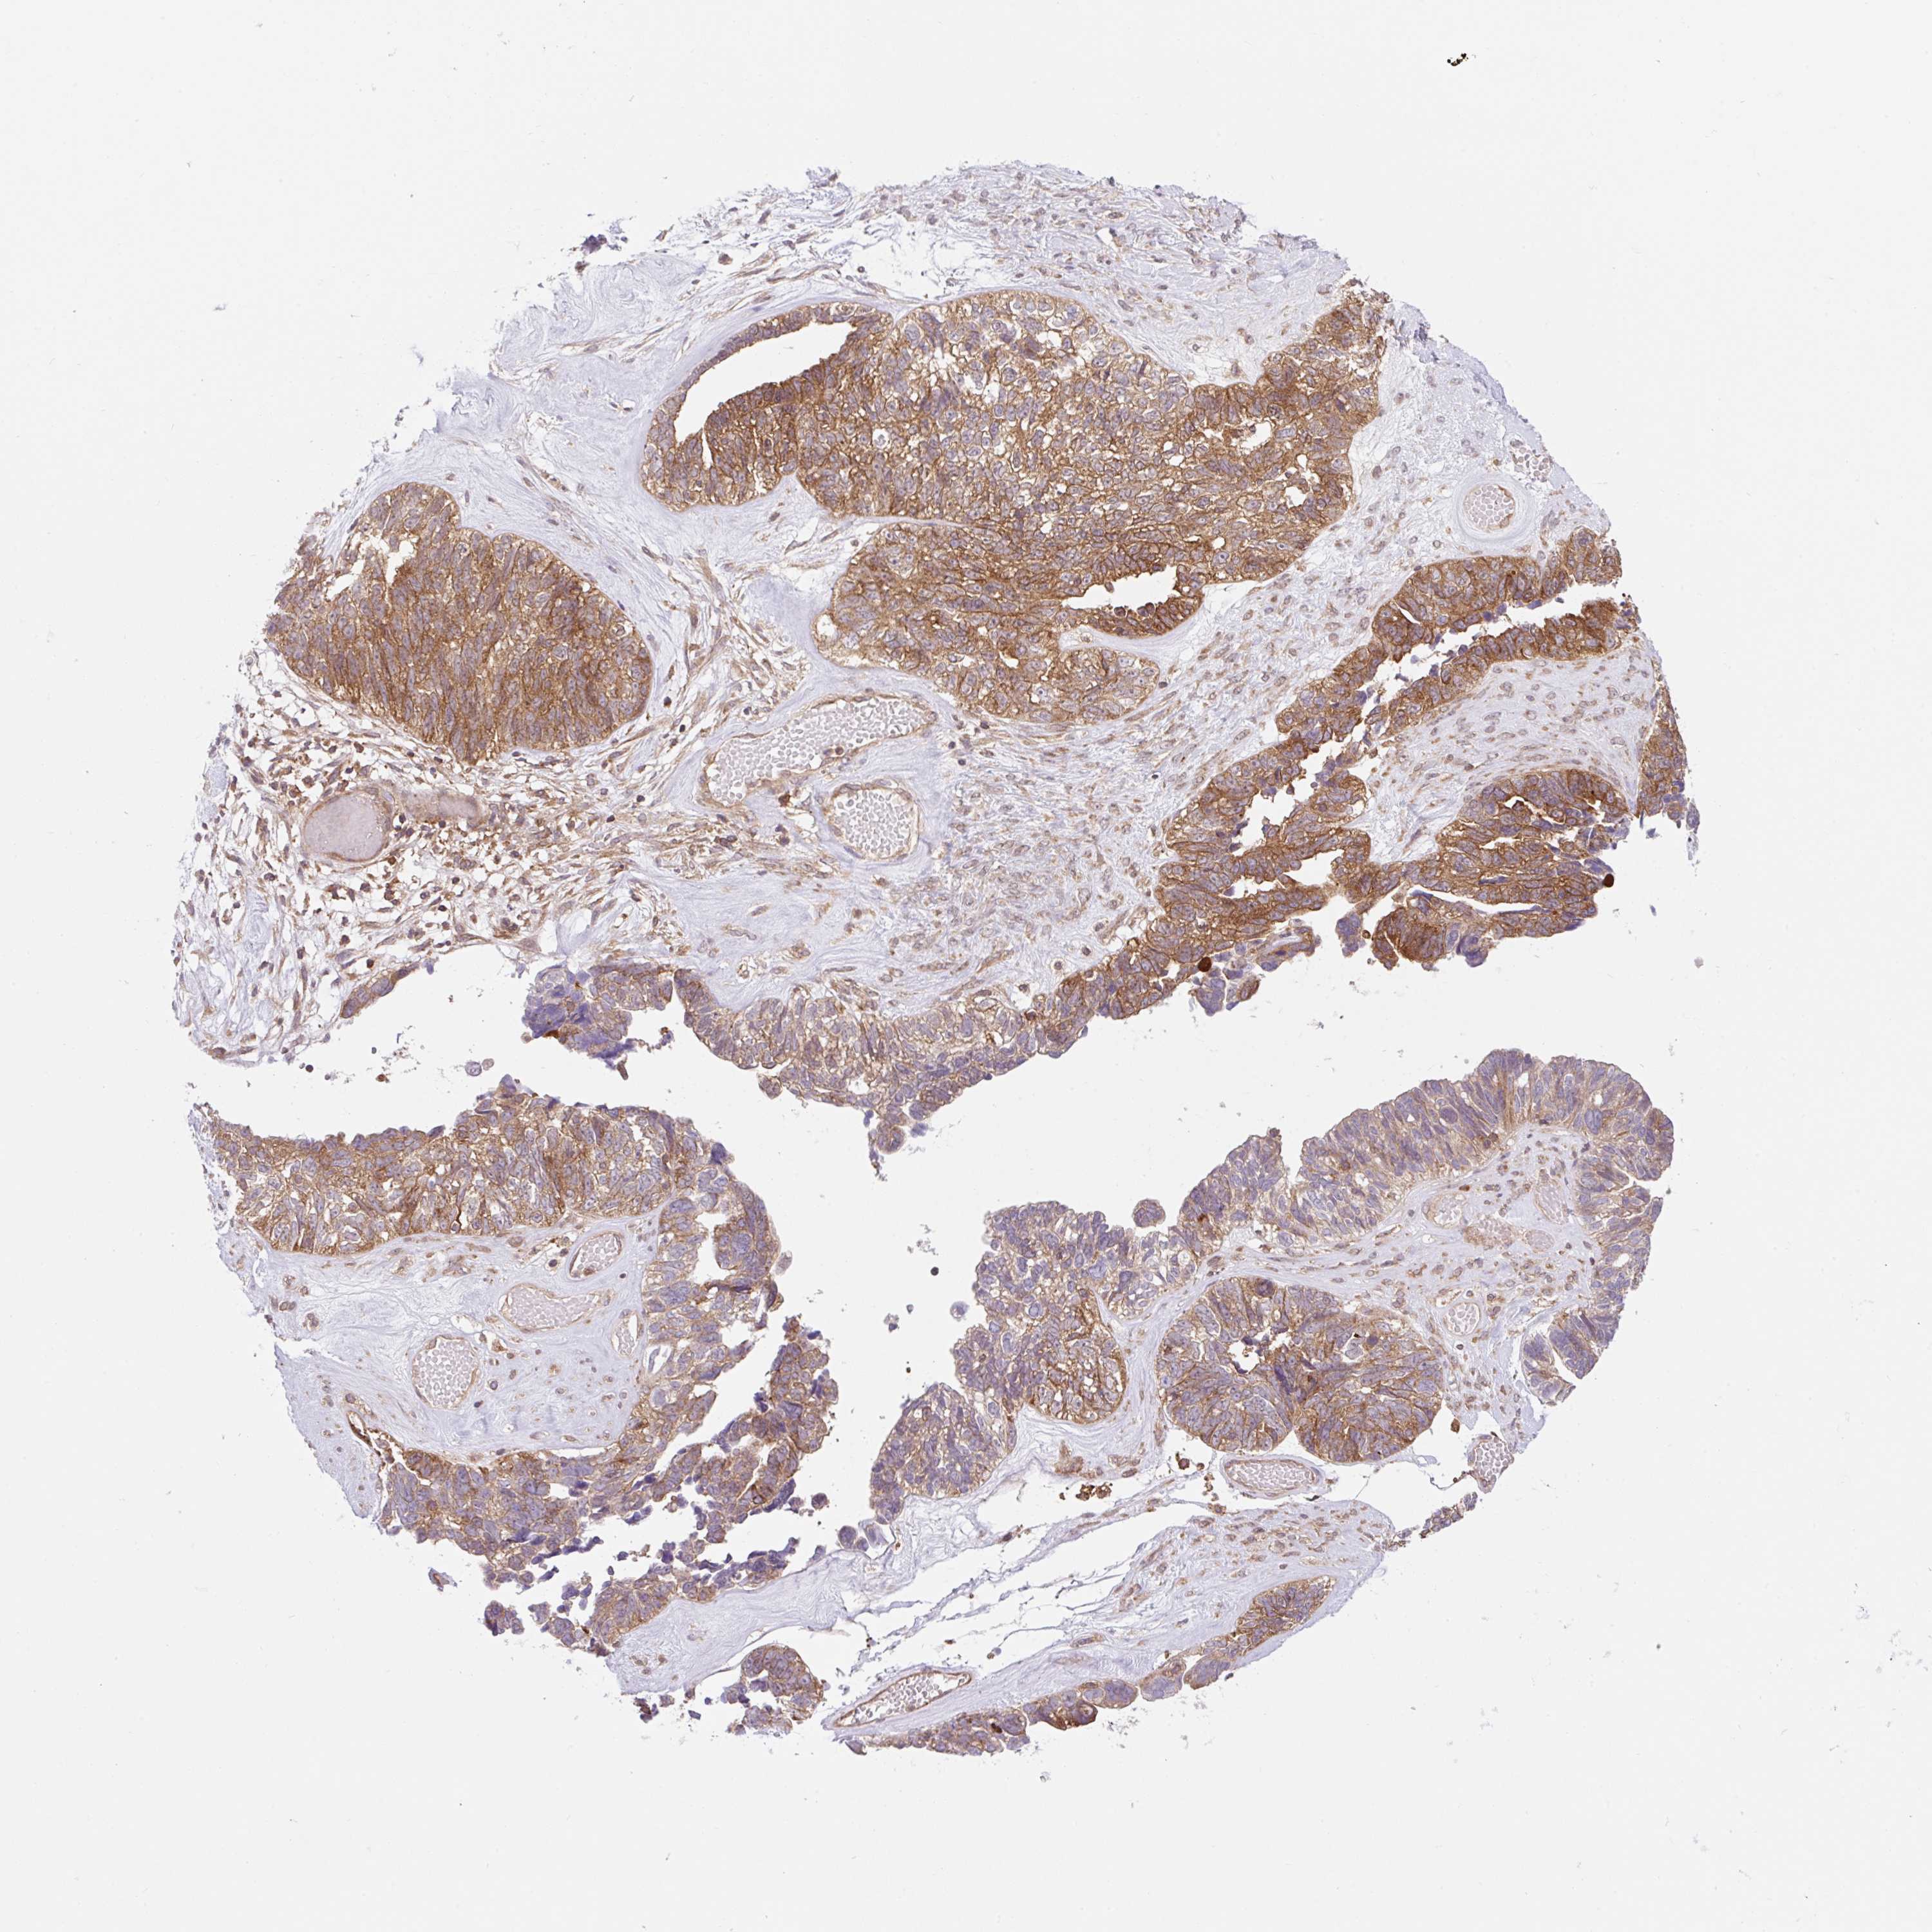

OVARIAN CANCER - Protein expressioni

A mouse-over function shows sample information and annotation data. Click on an image to view it in a full screen mode. Samples can be filtered based on level of antibody staining by selecting one or several of the following categories: high, medium, low and not detected. The assay and annotation is described here.

Note that samples used for immunohistochemistry by the Human Protein Atlas do not correspond to samples in the TCGA dataset.

Antibody stainingi

Antibody staining in the annotated cell types in the current human tissue is reported as not detected, low, medium, or high, based on conventional immunohistochemistry profiling in selected tissues. This score is based on the combination of the staining intensity and fraction of stained cells.

Each image is clickable and will lead to virtual microscopy that enables deeper exploration of all samples and also displays staining intensity scores, fraction scores and subcellular localization as well as patient and tissue information for each sample.

Antibody CAB034411

Cystadenocarcinoma, serous, NOS

Carcinoma, endometroid

Cystadenocarcinoma, mucinous, NOS

Carcinoma, NOS